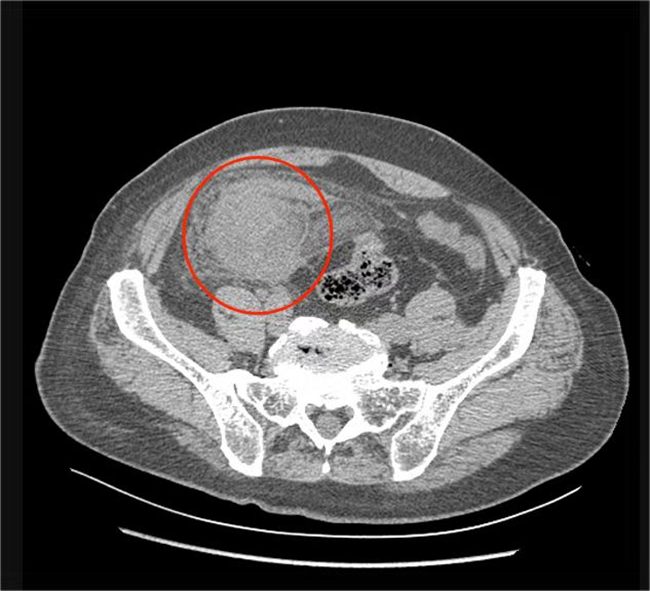

一个月前,我院发热门诊接收了一位特殊的病人,一位100岁的老人因为发热、咳嗽3天来医院就诊,完善相关检查后,以肺炎收入了我院呼吸科。呼吸科医生在查体时发现老人肚子上有一个明显的包块。CT检查结果提示患者右下腹占位,直径约8厘米。普外科张军主任团队对患者进行会诊后,考虑不能排除阑尾周围脓肿合并严重感染的可能。